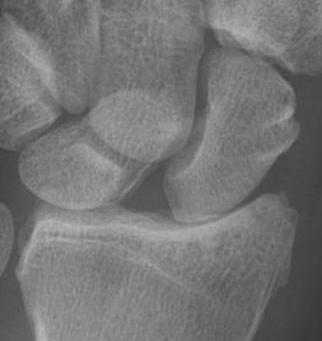

X-ray

Scapholunate gap > 3 mm

AP

| Terry Thomas sign | Cortical ring sign | Scaphoid shortened |

|---|---|---|

|

Increased scapholunate interval > 3 mm compared with other side |

End on view of distal scaphoid due to flexion | Shortened due to flexion |